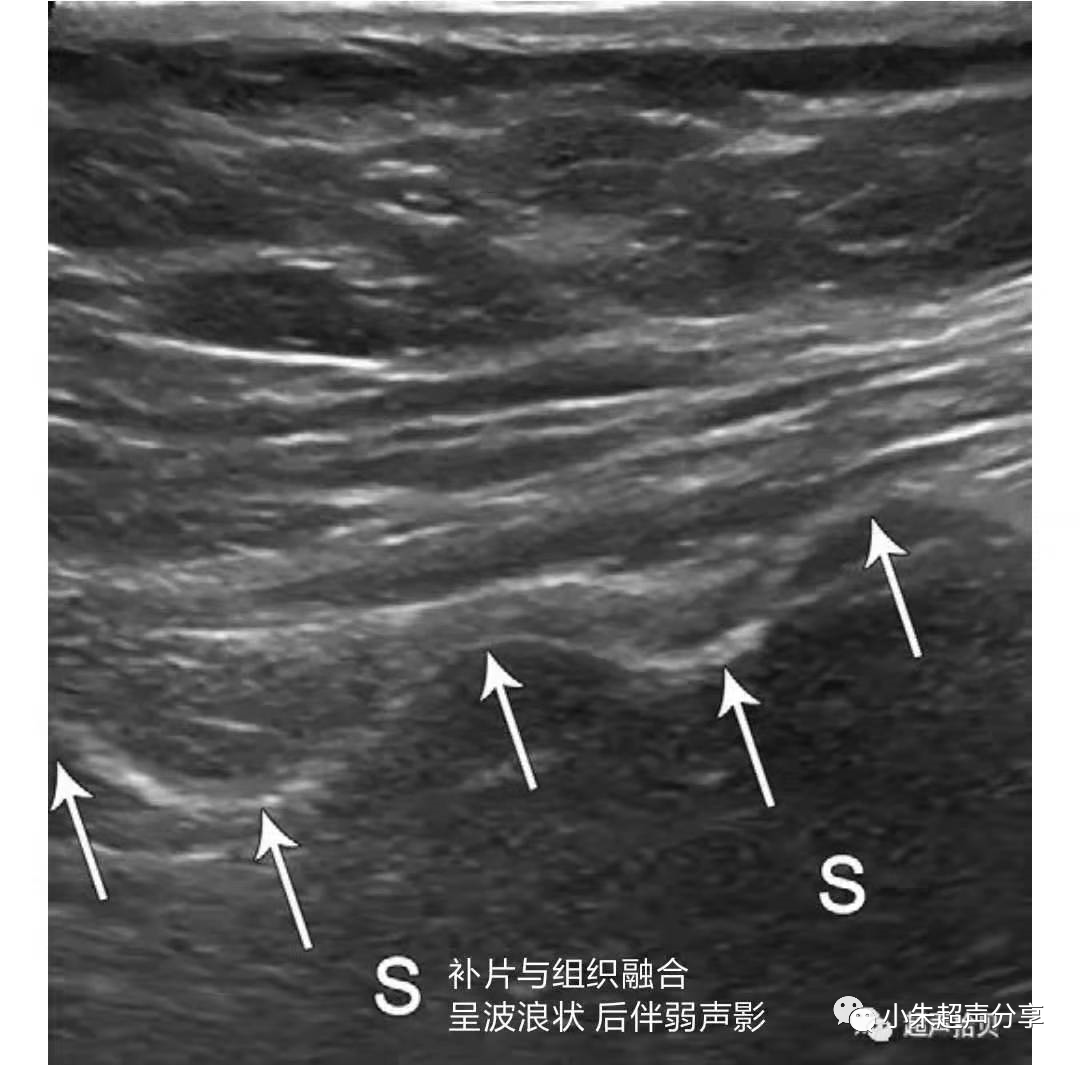

补片植入后,在缺损组织中起接作用。随时间推移,补片可以融合到愈合的组织中形成强健的支撑结构。这一愈合过程会导致补片皱缩,使其呈波浪状

超声检查时,置入的补片一般表现为条索样强回声,部分可伴弱声影,周围有积液时显示清晰,无积液衬托时常常显示欠清或难以显示。因补片类型及置入时间的不同,补片的形态亦会有所不同。